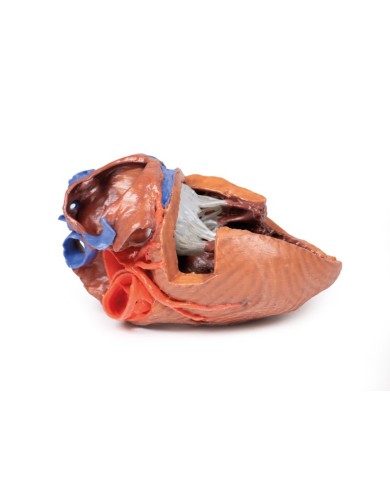

Modello di cuore di alta qualità scomponibile in 5 parti

Modello di cuore di alta qualità scomponibile in 5 parti

La parete anteriore del cuore è staccabile per poter vedere i ventricoli.

Modello anatomico di cuore, ingrandito 2 volte, su cavalletto

Questo modello dettagliato mostra, oltre alle strutture anatomiche del cuore, anche una parte del diaframma (base)

Realizzato in stampa 3D ad elevatissima risoluzione a colori.